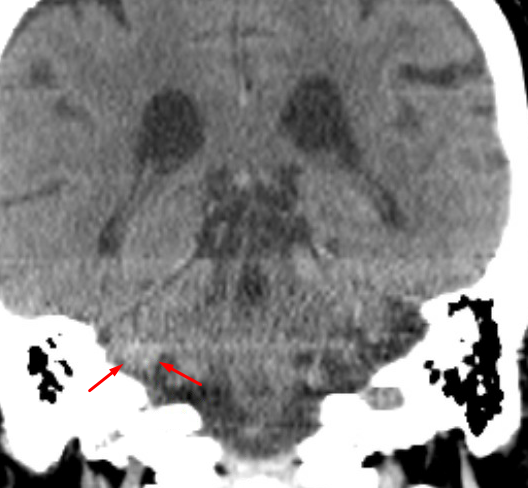

Age: 50

Sex: Female

Indication: Headache